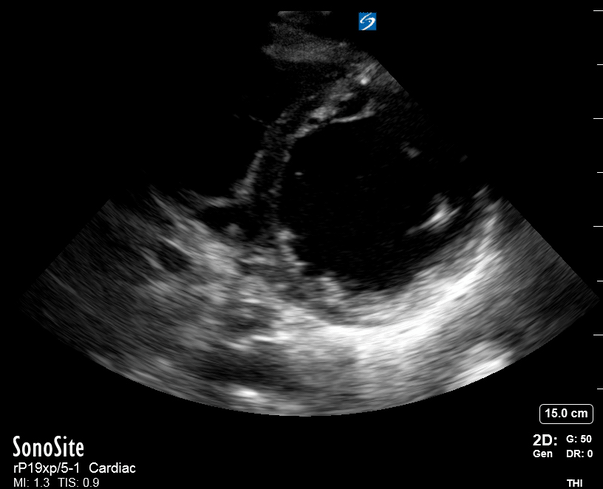

THE VIEWS

The PLAX view is versatile and allows the recognition of multiple landmarks, making it good for visual estimation of LV contractility. It is essential to optimize the view ensuring a true sagittal long axis, as being oblique to the LV chamber may underestimate its size and overestimate its emptying. The PSAX view at the level of the papillary muscles reveals the entire muscular circumference and concentric squeeze of the LV. It is useful to estimate both global function and focal wall motion abnormalities. The A4C view, although technically challenging, provides good insight into the global myocardial function and chamber size.

LV CONTRACTILITY

Qualitative assessment of the LV and visual estimation of Ejection Fraction is based on three parameters:

Endocardial excursion.

Myocardial thickening.

Movement of the anterior leaflet of the mitral valve.

A qualitative assessment is typically categorised as:

Normal (LVEF 50-65%)

Moderately Depressed (LVEF 30-50%)

Severely Depressed (LVEF < 30%)

Hyperdynamic (LVEF > 65%)